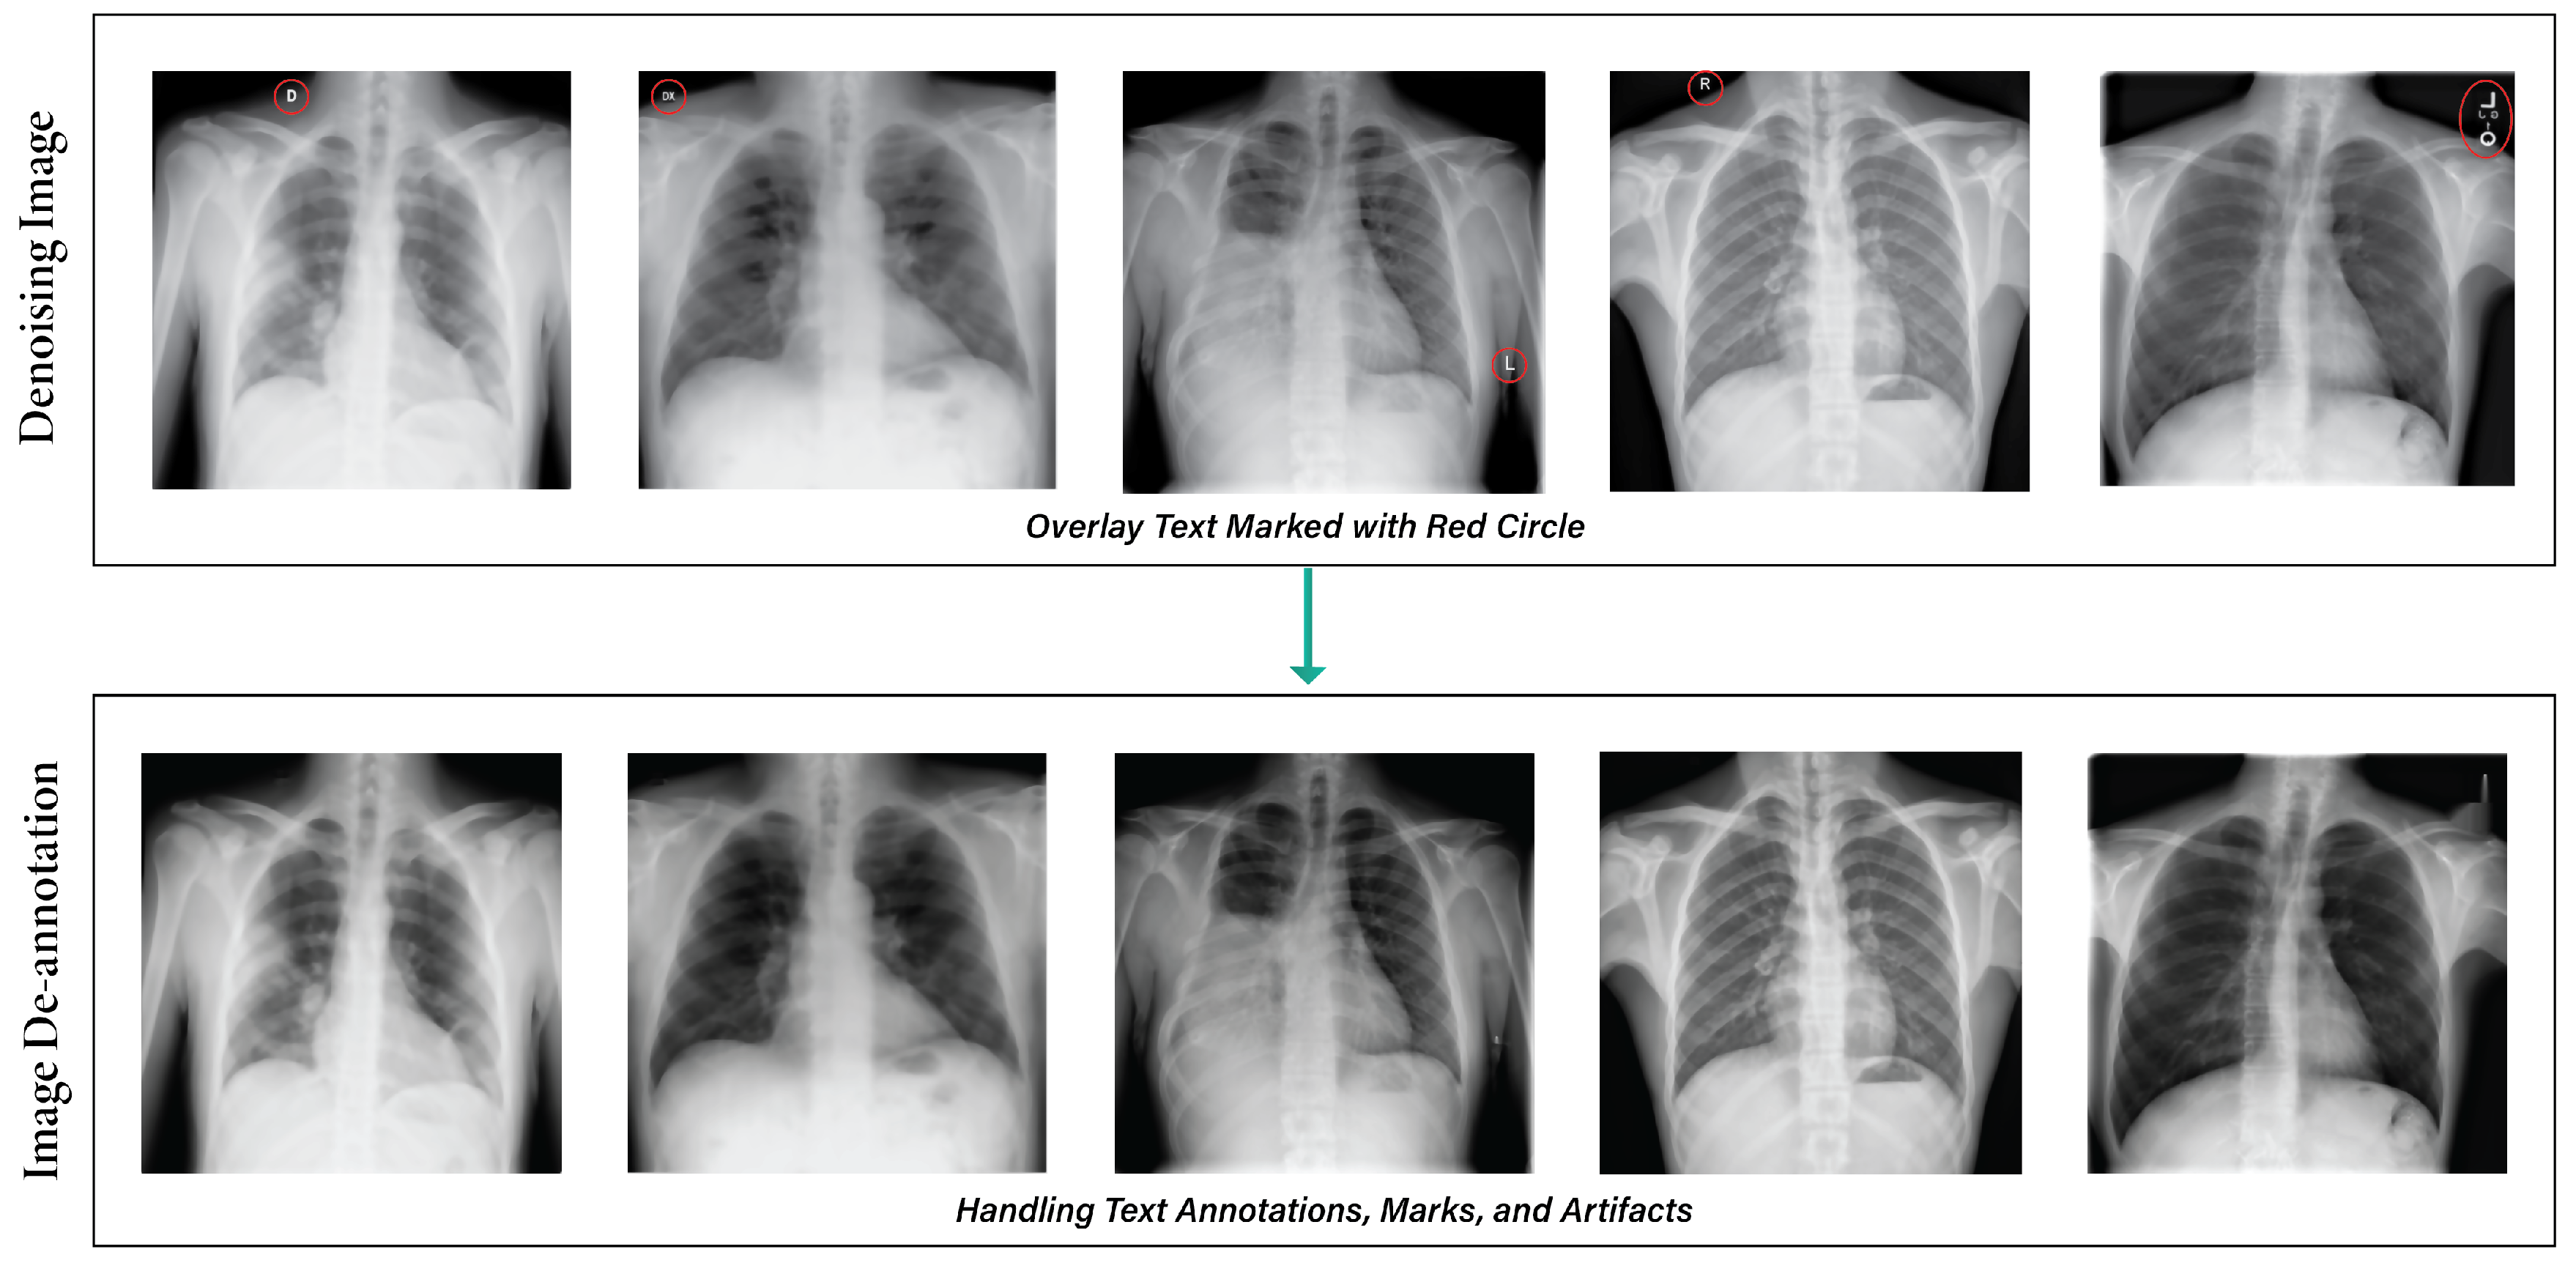

3.2.2. Image Denoising

3.2.3. De-Annotation

- Effective image pre-processing techniques improve lung disease classification accuracy by reducing noise and artifacts. In this regard, we resized all images to the same pixel. The de-annotation method improves images by removing annotations and extraneous text, and the enhancement method enhances image properties. We used elastic deformation methods to add random distortions to the data to balance the distribution of underrepresented class images.